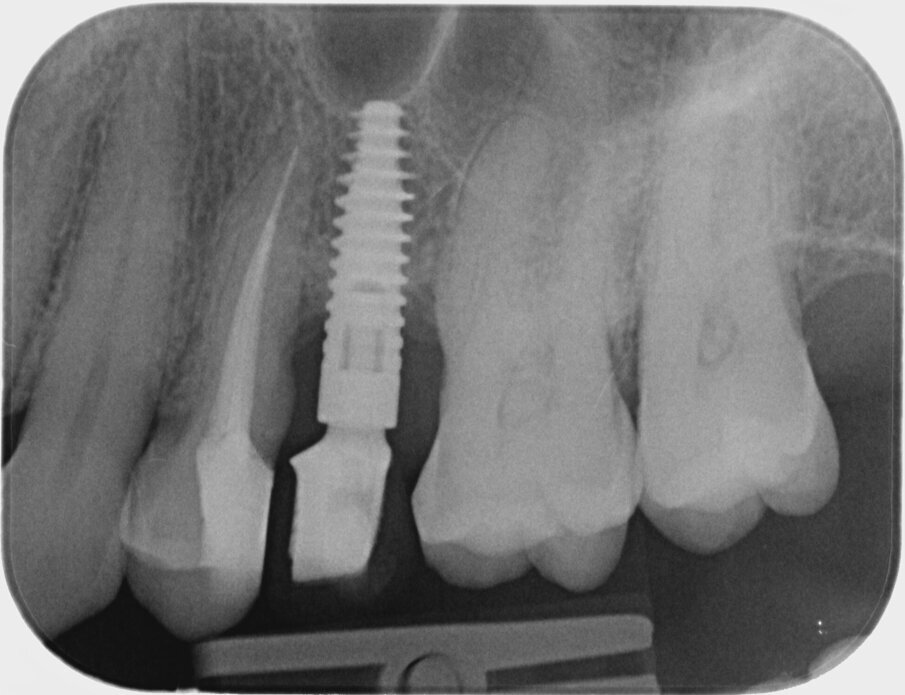

Quinta e sesta seduta A 90 gg si effettua seduta di richiamo con deplaquing, privilegiando l’impiego di polvere di glicina con sistema air polishing (CombiTouch Mectron Spa) con multidirezionalità del getto prima in senso apico-coronale, poi in direzione corono marginale e infine perpendicolare alla superficie implantare esposta, con l’obiettivo di decontaminarla al meglio, senza ledere i tessuti circostanti. A 6 mesi dal baseline (t4) si esegue la rivalutazione. Vengono eseguite fotografia e rx endorale del sito di controllo (Figg. 5, 6). All’esame visivo e palpativo i tessuti molli perimplantari si presentano in buono stato, in termini di colore e consistenza. All’esame radiografico si apprezza una remineralizzazione dell’osso. Viene eseguita la terapia professionale mediante la medesima tecnica di air polishing con polveri a bassa granulometria, al fine di disgregare l’eventuale biofilm patogeno, potenziale causa di recidiva. In entrambe le sedute viene eseguito un rinforzo motivazionale.

Fig. 6

valutazione radiografica del sito implantare trattato (Fig. 8);

Fig. 8

È possibile apprezzare radiograficamente un’aumentata mineralizzazione ossea, con un ulteriore miglioramento rispetto alla prima rivalutazione post-terapia. Questo dato indica la risoluzione dello stato infiammatorio cronico e conferma il buon potenziale rigenerativo della terapia adottata. Contestualmente, all’esame visivo dei tessuti, si osserva un riposizionamento in direzione coronale del tessuto molle, con un aumento dei volumi gengivali rispetto al tempo t4, anch’esso indicativo del potenziale rigenerativo stimolato dalla strategia terapeutica a livello del tessuto connettivo gengivale.

In particolare, nel caso in oggetto, l’associazione tra rimozione del biofilm batterico tramite curettes manuali/ulttrasoniche ed air polishing con polvere di glicina e terapia fotodinamica con acido 5-aminolevulinico (ALA), si è rivelata efficace nel promuovere remineralizzazione dell’osso, osservabile già al controllo radiografico a sei mesi e ancor meglio nella rivalutazione a 24 mesi. La risoluzione dell’edema,il miglioramento nell’aspetto clinico e il ripristino del tono dei tessuti molli peri-implantari sono segni clinici di guarigione e stabilizzazione inconfutabili.